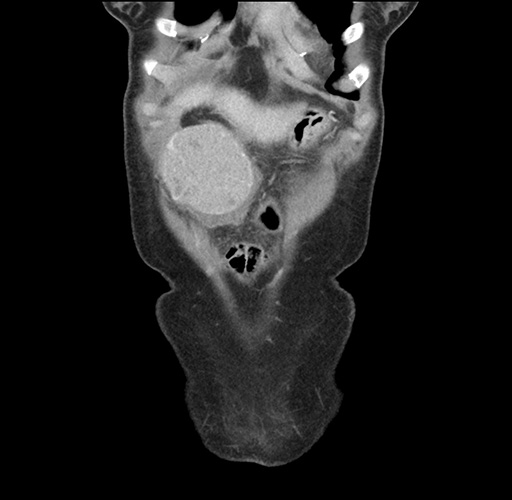

Imaging Analysis

Look through the patient's CT scan to identify any areas of concern for the necessary procedure.

Based on your CT findings, which issue(s) would give reason for "planned slowing down moment(s)" in this case?

Considering a standard left lateral sectionectomy procedure, what step(s) of the operation would you do differently in this case ?